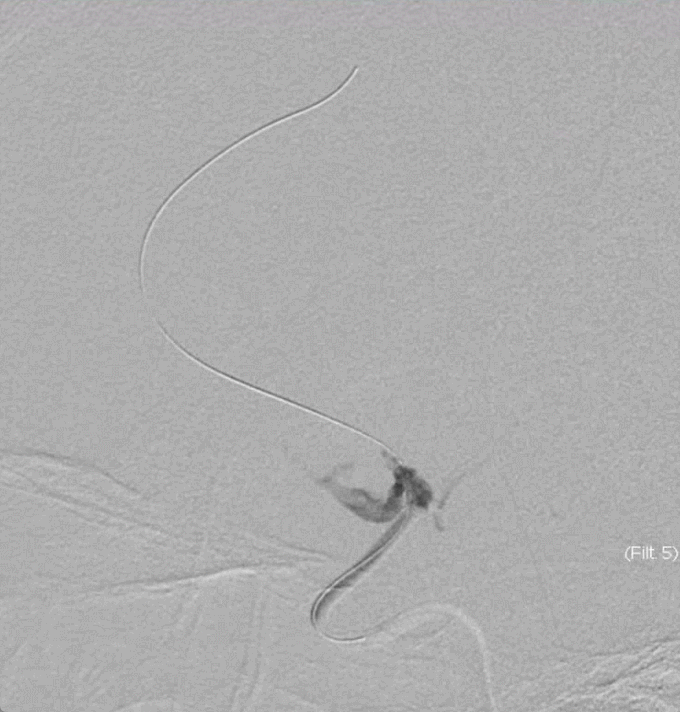

长鞘+125cm Tethys®中间导引导管+2m 0.014inch导丝+微导管。

微导管顺利进入大脑前动脉。

125cm Tethys®中间导引导管顺利过眼动脉弯。

微导管造影明确闭塞血管情况。

微导管到达远端。

释放3×20mm取栓支架。

支架锚定后,Tethys®中间导引导管顺利进入大脑前动脉。

继续跟进Tethys®中间导引导管。

抽拉结合。

血流恢复。

观察血流。

3D造影,弹性回缩明显。

引入2.5×20mm支架并释放。

支架植入术后。

血管维持可。